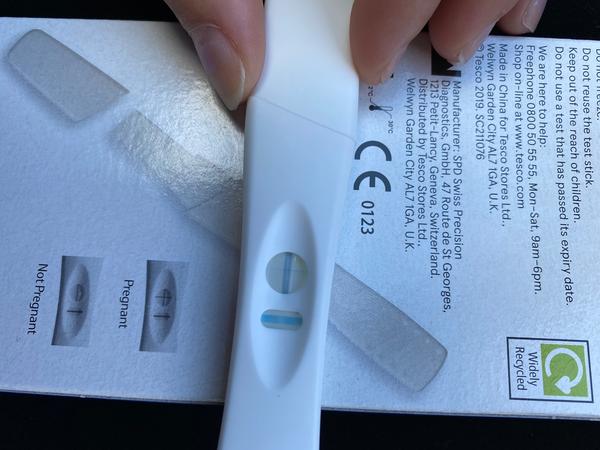

@lowndes unavená som dosť prsia cítim take naliate ale to mavam aj pred menštruáciou kríze a podbrusko take normálne ako pred menštruáciou skôr ze aom dosť unavená co ja nikdy nebyvam 😊

Ahojte baby tak mne meškala ms 4 deň už som sa začala tešiť že to vyšlo . Až na dnes som to dostala . Včera test. Negatívny 🙄 2 roky snaženia už asi vzdávam